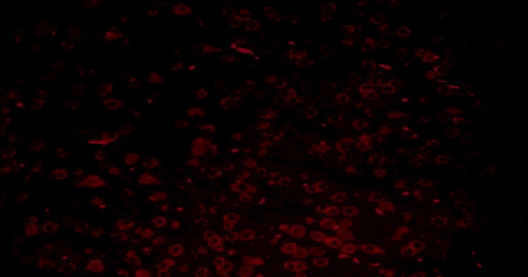

TEL increased NeuN expressions in MPTP intoxicated mice brain

SNpc and ST regions of MPTP mice brain showed a significant decrease in % NeuN immunopositive cells [F (4,10) = 274.1, p<0.01 and F (4,10) = 86.24, p<0.01, respectively] when compared to the vehicle treated mice. TEL (3 and 10 mg/kg) significantly (p<0.01) increased % NeuN immunopositive cells in both the regions in comparison to MPTP mice (fig. 4).

Fig. 4: Effect of TEL on % NeuN immunopositive cells in MPTP intoxicated mice brain. Pictures represent NeuN immunopositive cells of (A) SNPc and (B) ST brain regions X 400 magnification. (1) Normal control, (2) MPTP induced mice brain, (3) TEL (3 mg/kg b. wt.) administered MPTP mice brain, (4) TEL (10 mg/kg b. wt.) administered MPTP mice brain and (5) TEL (10 mg/kg b. wt.) administered normal mice brain. (C) Values were expressed in mean±SEM, n=4 animals/group, statistical analysis was performed using one way ANOVA followed by Tukey’s multiple comparison test, ## indicates p value<0.01 Vs group I, ** indicates p value<0.01 Vs group II